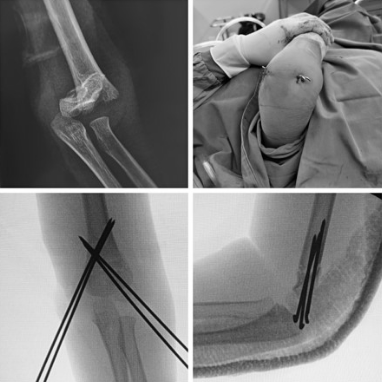

「一微一防」指的是针对儿童肱骨髁上骨折,我们采用闭合复位克氏针微创内固定的方法,该术式操作时间短、手术创伤小、局部血运影响少、并发症发生率低、术后恢复快,疤痕小,几乎不影响美观。闭合复位,微创固定必须使用 X 光透视,我们特别重视术中患儿 X 光暴露的防护,采用屏蔽防护、时间防护两种方法。

屏蔽防护是指在术中 X 线透视过程中,给予患儿铅衣覆盖保护,仅暴露手术区,减小暴露于 X 线照射的范围。时间防护是指结合创伤团队丰富的手术经验和熟练的闭合复位技术,尽量缩短 X 线照射时间,双管齐下,从而减少 X 线对患儿的损伤。